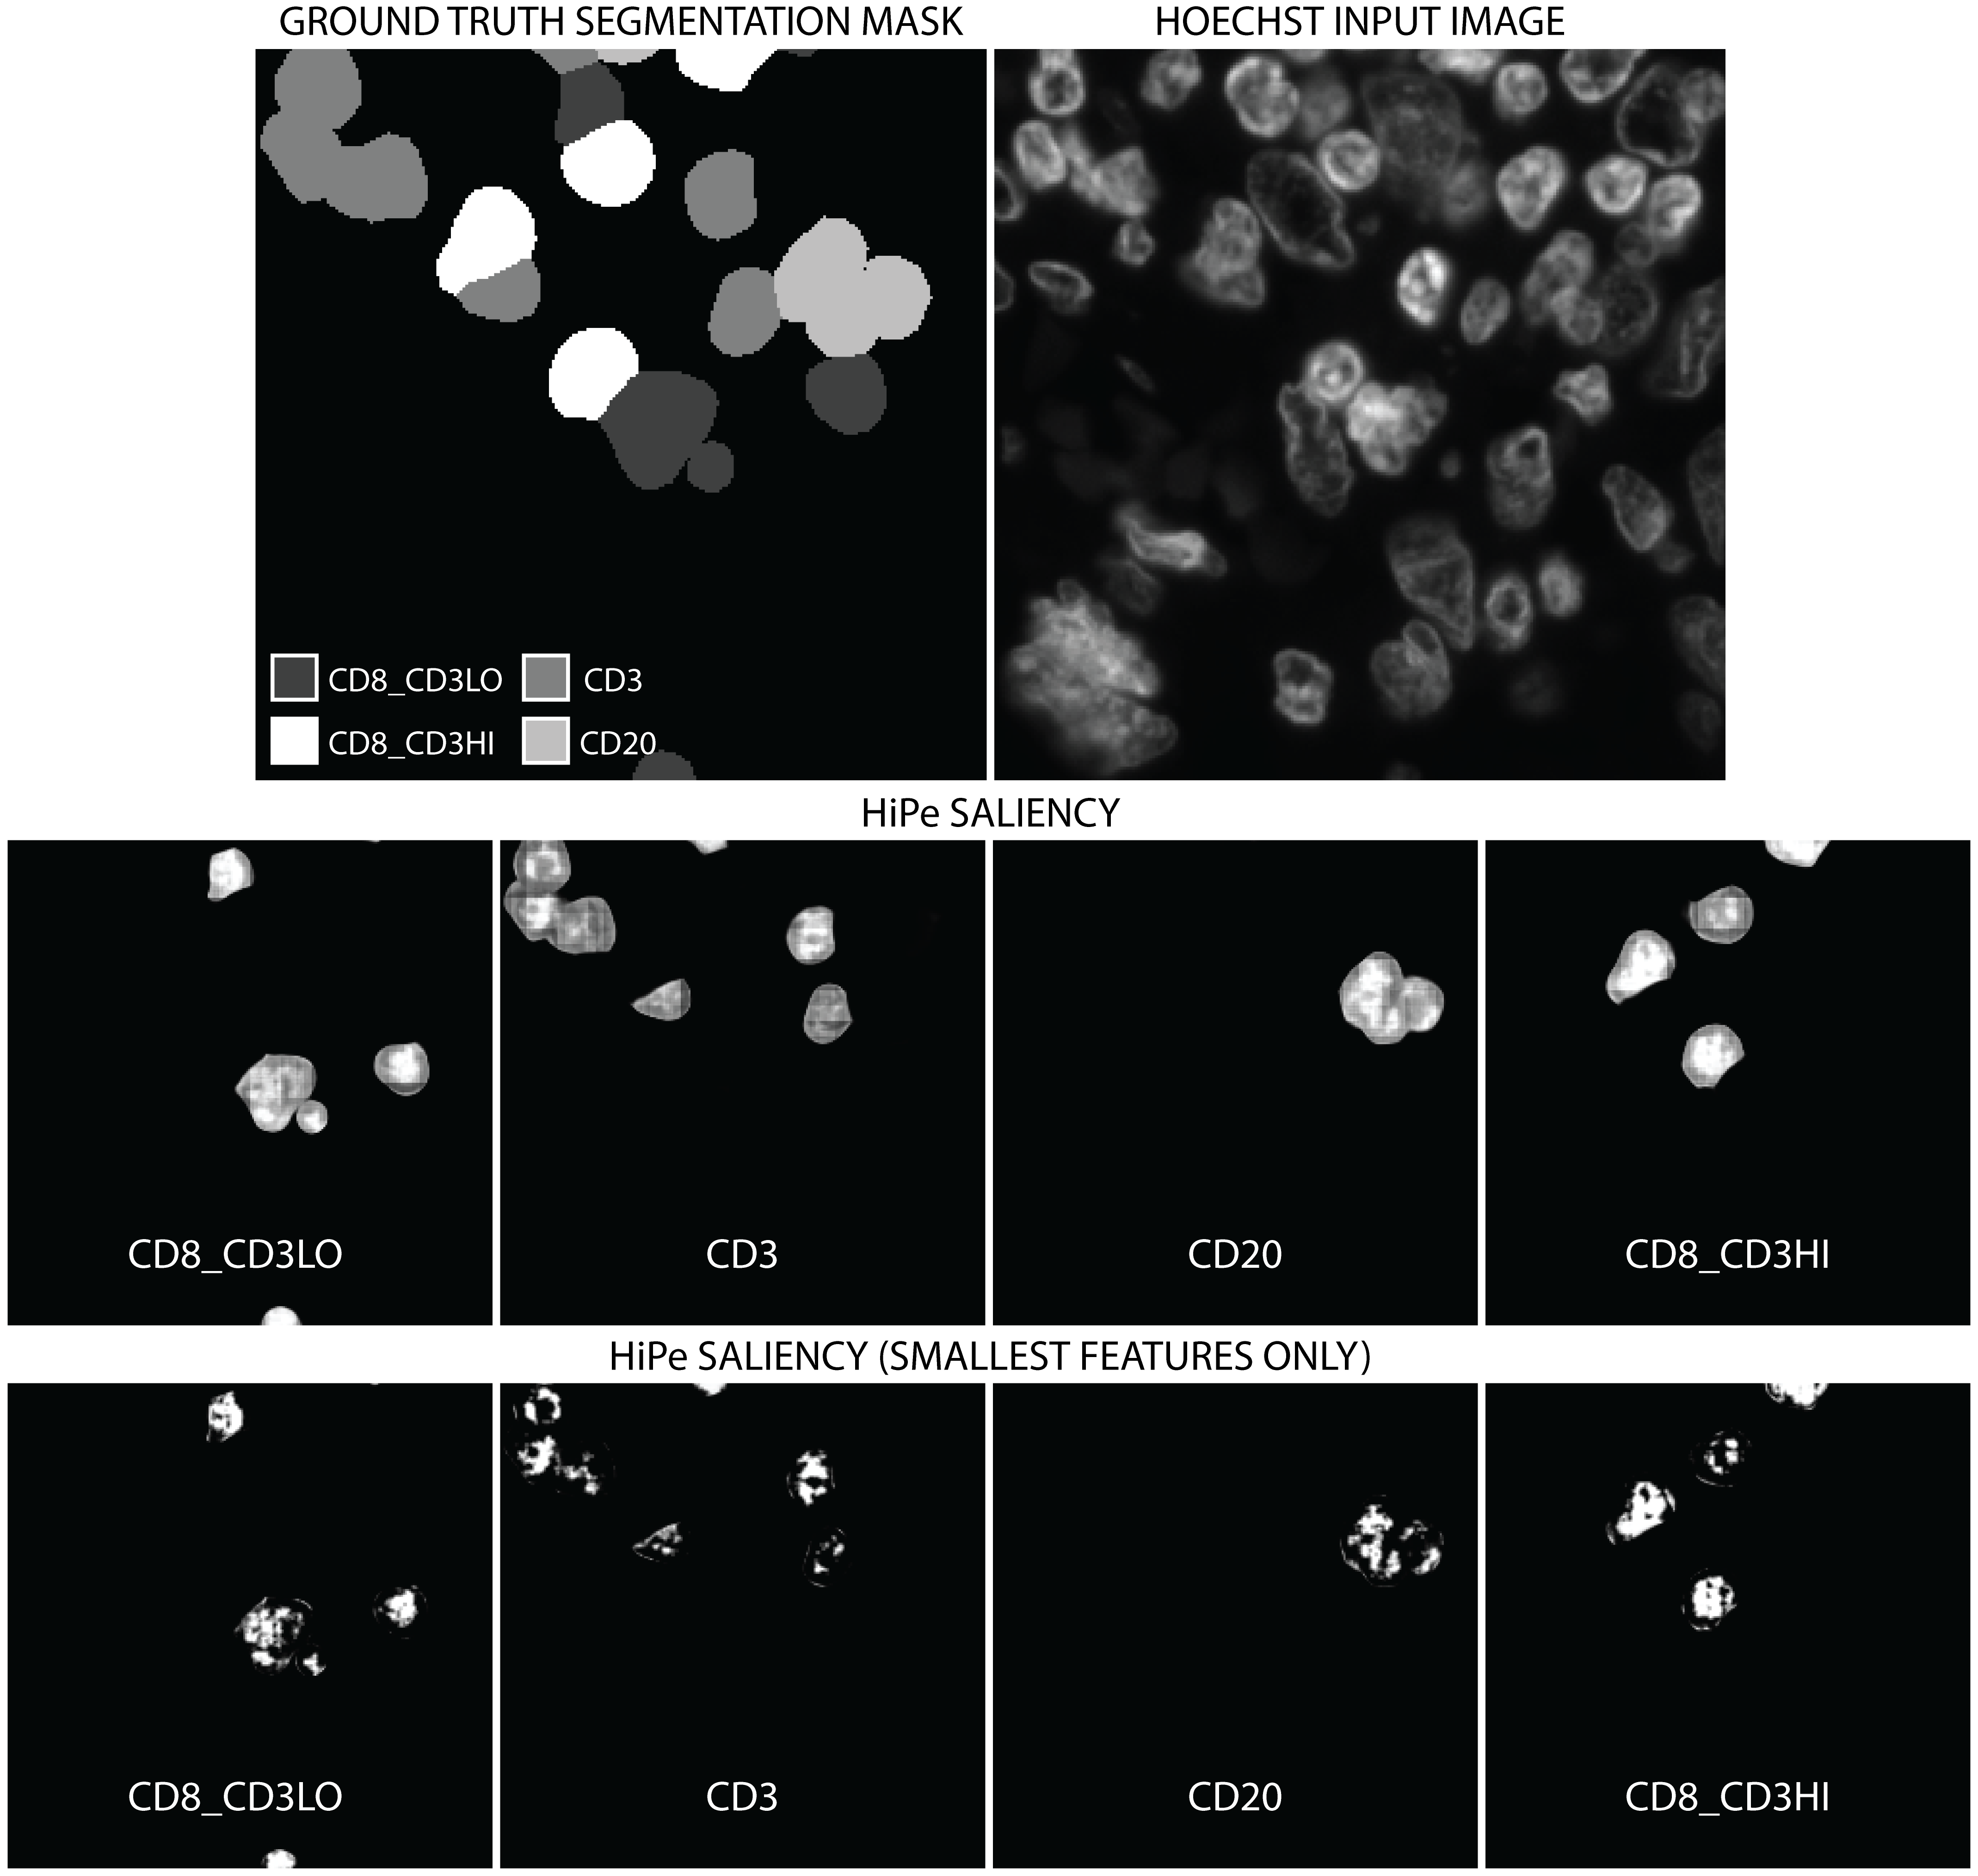

To gain further insight into the learned features, we used Hierarchical Perturbation [8] (HiPe) to generate saliency maps – visualisations of which regions of the input image were more or less important in determining the ultimate output of the model – at different resolutions, as shown in Figure 4. We used the standard implementation of HiPe on the softmaxed output of the model, with “fade” perturbation (such that occluded portions are replaced with zero input) and four initial cells. Input saliency based methods like HiPe are more transparently interpretable than input optimisation, as they explicitly show which areas of the input image were more or less important in determining the output for each class. We use HiPe in preference to other input saliency based explanatory techniques as it is much quicker than similar perturbation-based saliency methods for multiple large images containing relatively small salient features, as is the case with WSIs, and is more precise than gradient-based methods which are often indistinct.

We found that larger salient regions were comprised of the cells themselves, as would be expected – but more interestingly, that the most salient regions were smaller, appearing to cluster in the nuclei of the salient cells. This supports our conclusion that the model is using morphological features of the chromatin made visible by Hoechst 33342 staining to perform the classification. We also note that the model does not find regions outwith the cells in question salient, showing that the proximity or morphology of nearby cells or tissue structures is not used to inform the segmentation at all.